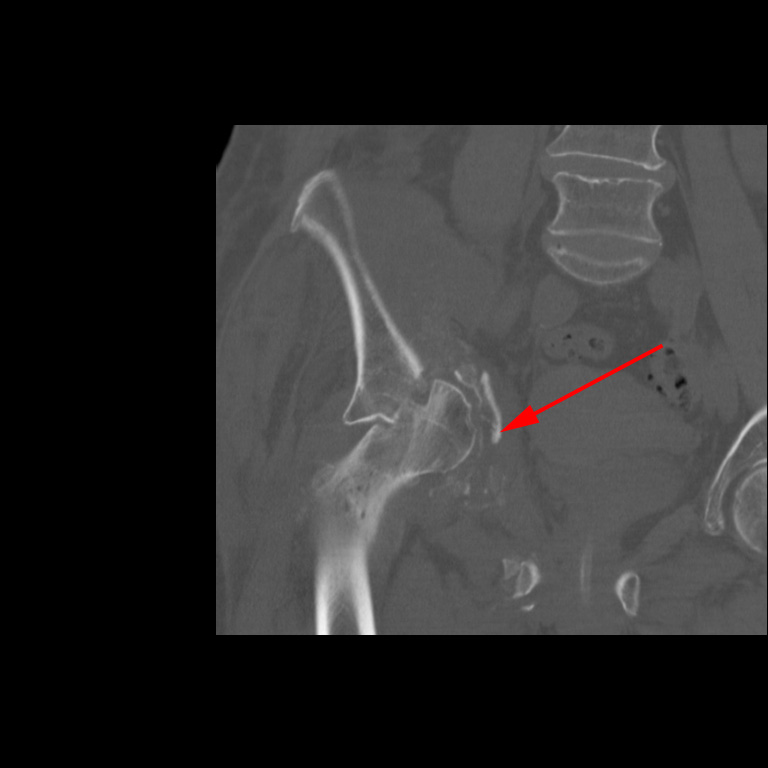

CT-skanning af højre hofte, der viser knusning af acetabulum (rød pil).